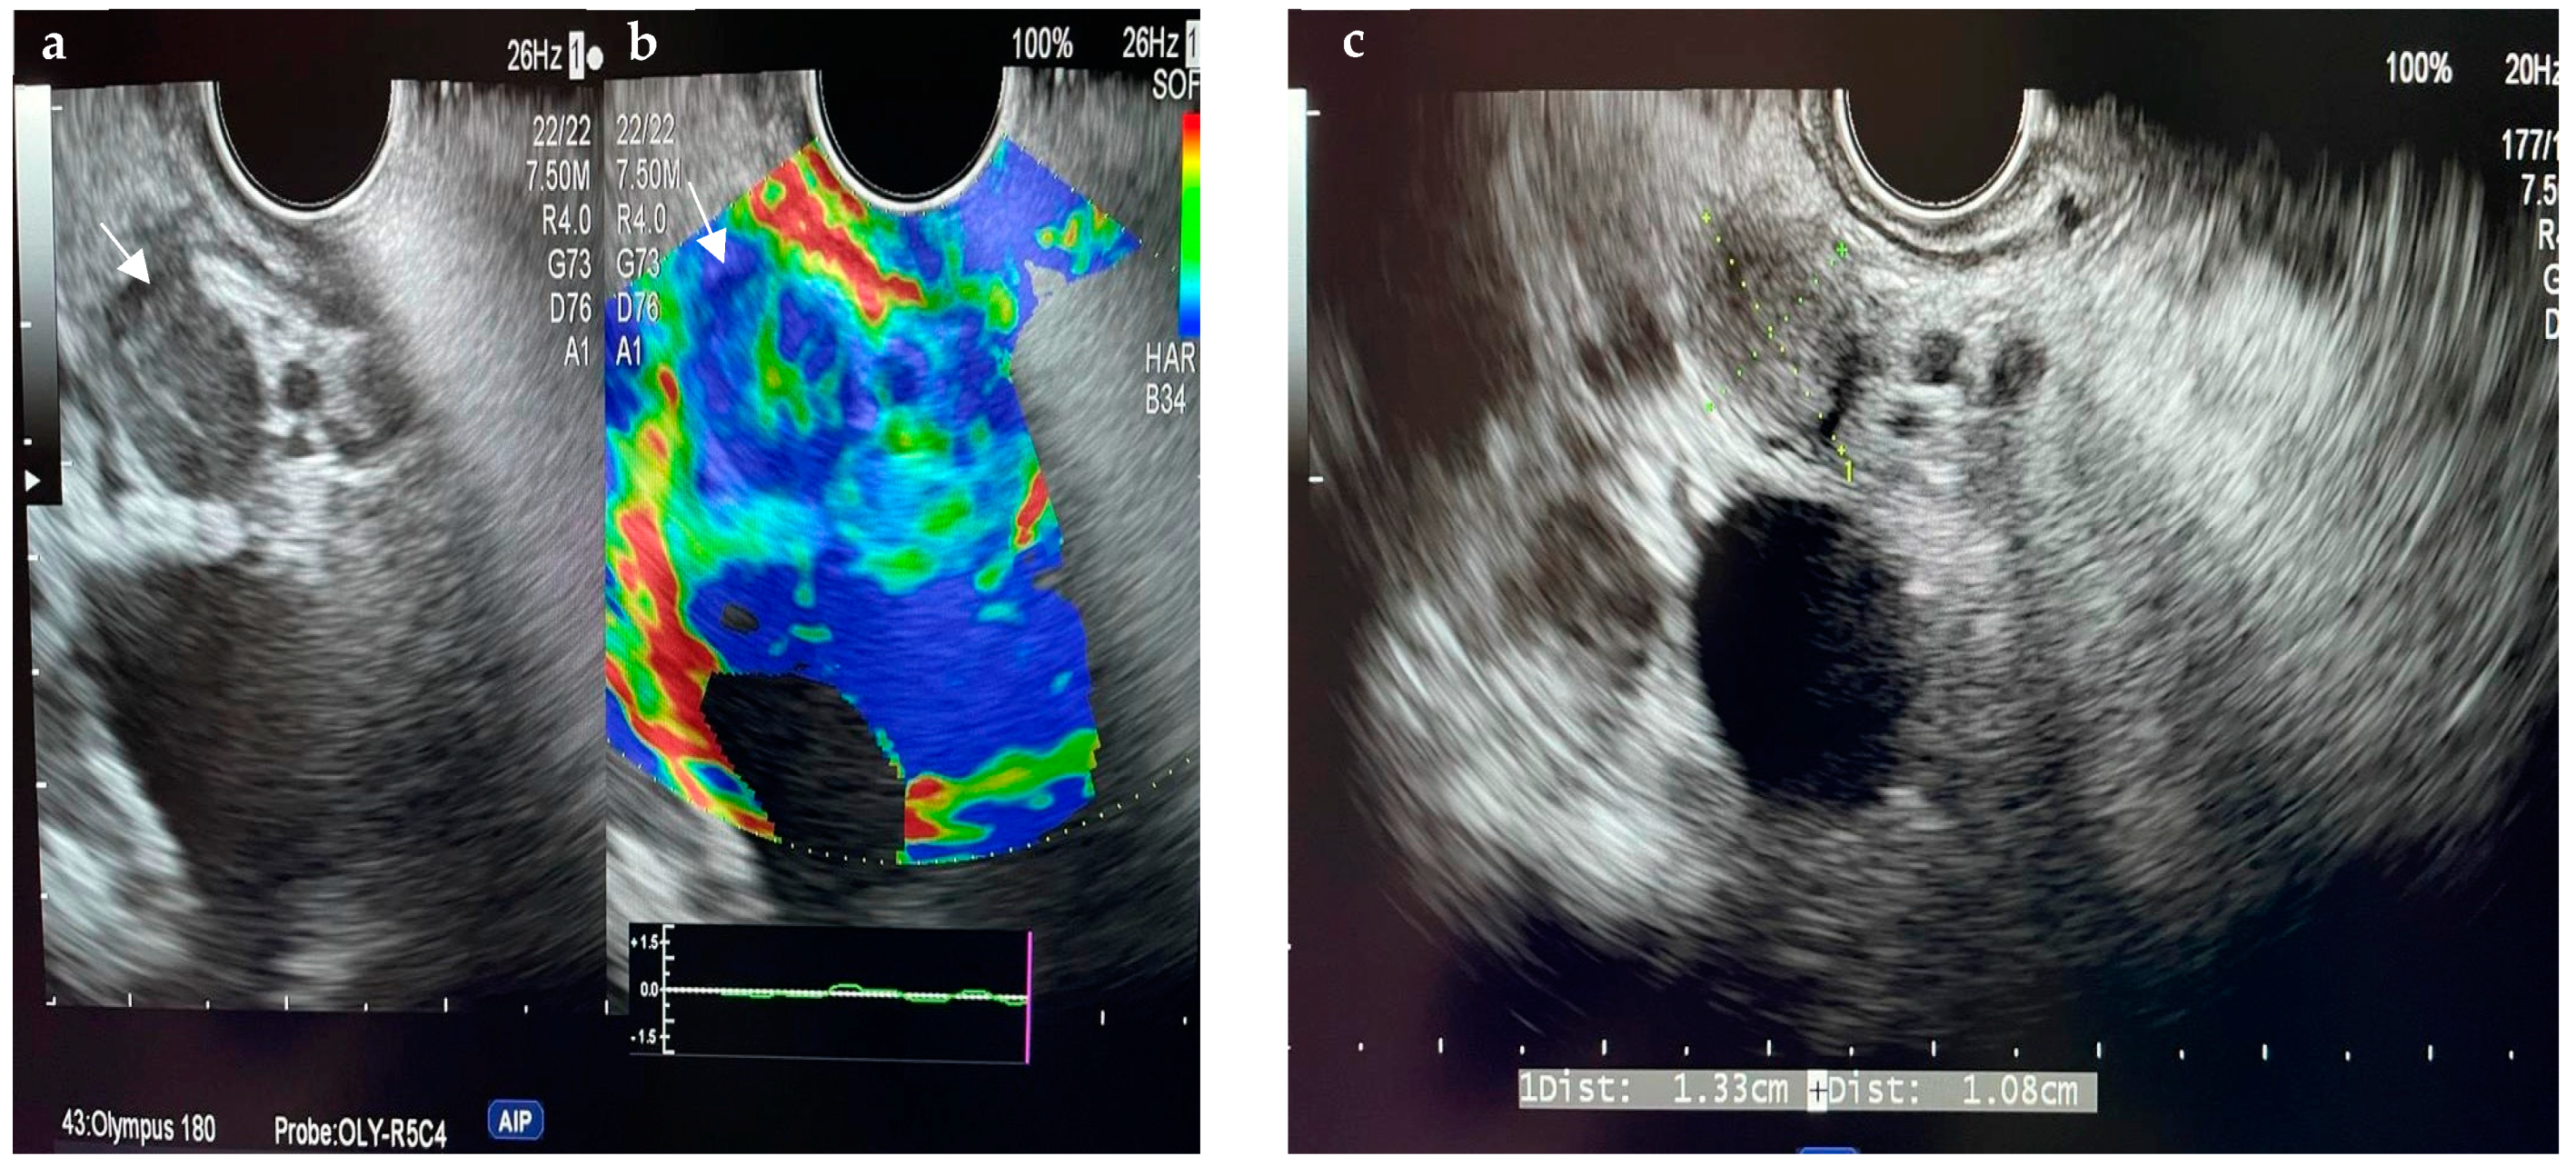

6.4.1. Endoscopic Ultrasound (EUS)

- Otsuka, Y.; Kamata, K.; Hyodo, T.; Chikugo, T.; Hara, A.; Tanaka, H.; Yoshikawa, T.; Ishikawa, R.; Okamoto, A.; Yamazaki, T.; et al. Utility of contrast-enhanced harmonic endoscopic ultrasonography for T-staging of patients with extrahepatic bile duct cancer. Surg. Endosc. 2022, 36, 3254–3260. [Google Scholar] [CrossRef] [PubMed]